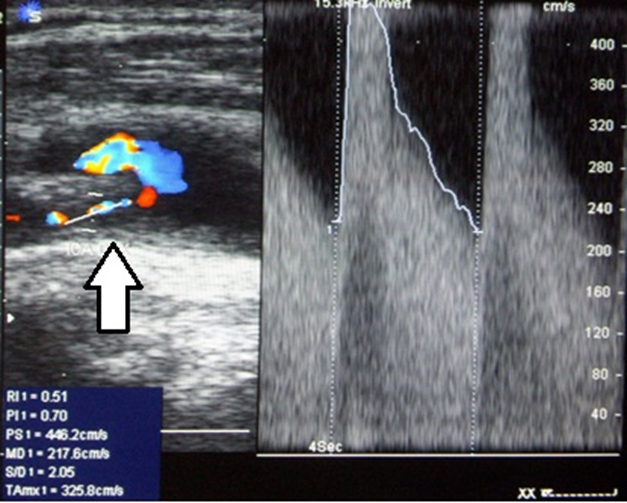

Рисунок 3 - Пациент В., 67 лет, с ишемическим инсультом, осложнившимся геморрагической трансформацией очага ишемии после тромболитической терапии

Примечание: Дуплексное сканирование сонных артерий на экстракраниальном уровне: стеноз правой ВСА 80% (NASCET) с ускорением систолической скорости кровотока до 446 см/с и диастолической скорости кровотока до 217 см/с (стрелка)